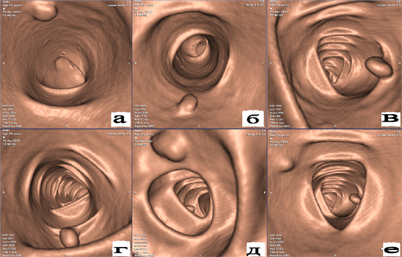

Рассмотрим более детально метод колоноскопия, и что даёт нам такое обследование. Колоноскопия - это исследование толстой кишки специальным зондом. Для более ясной картины осветим алгоритм выполнения процедуры. Обследование проводиться с помощью миниатюрной камеры расположенной на специальном зонде (трубке), которая введена в прямую кишку, через анальное отверстие. Пациент располагается на кушетке в горизонтальном положении, покручиваясь на бок. Процедура проводиться вполне безболезненно, так как пациент принимает снотворное, и быстро погружается в кратковременный сон. Продолжительность сна, соответствует времени проведения обследования. При помощи крошечной эндоскопической камеры, которая постепенно продвигается внутри толстого кишечника, доктора детально изучают внутрение стенки кишечника. Для выравнивания кишечника через зонд подаётся воздух. Глубина введения зависит от протяженности кишечника. Изображение подаётся на экраны мониторов в многократном увеличении. Пациент пробуждается по окончанию процедуры и получает готовые результаты обследования.

Колоноскоп - длинная трубка с маленькой камерой и подсветкой. Длина зонда составляет около 160 см. Внутри трубки имеются дополнительные каналы для специального оборудования, которое проводит при необходимости биопсию (иссечение кусочка ткани при подозрении на новообразования). С помощью дополнительных приспособлений возможно останавливать кровотечение или получить исследуемый материал (для дальнейшего изучения). Помимо колоноскопа используют фиброколоноскоп, им проводится фиброколоноскопия (ФКС). Этот метод является аналогом колоноскопии, но именно с его помощью можно извлечь материал для биопсии.

Колоноскопия или МРТ, что лучше

Вопрос очень щепетильный, так как ответить на него однозначно невозможно. Магнитно-резонансная томография - это вполне безопасный и действенный метод. МРТ позволяет сделать качественные снимки тонкой и толстой кишки. Под воздействием магнитного поля "считывается" и записывается информация. Этот метод ещё называют виртуальной колоноскопией.

Для полноценной картины сравним эти методы по отдельным критериям. При помощи колоноскопии можно не только обследовать толстую кишку на заболевания (полипы, язвы, раковые опухоли, дивертикулы и т.д.), но и устранить патологию, например: удалить полип, извлечь инородное тело, провести биопсию, или устранить внутреннее кровотечение толстого кишечника. Провести оценку цвета внутренней слизистой оболочки.